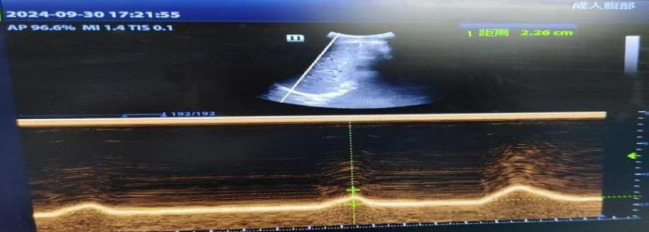

评价分级运动康复对AECOPD患者膈肌功能、运动功能及呼吸功能的改善效果。遵义市某三级医院呼吸重症监护科收治AECOPD患者68例。将患者随机分为研究组和对照组(每组34例),再根据分级标准将每组患者分为3个级别,共6组。对照组采用常规康复治疗,研究组采用分级运动康复治疗。采用床边超声监测两组患者康复前后膈肌功能(DE、DTei、DTee、DTF)、6MWT、CAT评分、mMRC问卷、无创机械通气时间、住院时间的变化。与康复干预前比较,研究组膈肌运动较对照组有显著改善(P < 0.05),但干预前有改善。分级运动康复能有效改善患者整体膈肌功能,对提高运动质量和耐力有积极作用;床边超声可以动态、实时观察AECOPD患者膈肌运动状态,客观、直接评价呼吸肌功能恢复情况,具有重要的临床价值。

To evaluate the improvement effect of graded exercise rehabilitation on diaphragm function, exercise function, and respiratory performance in AECOPD patients. 68 AECOPD patients admitted to the Respiratory and Critical Care Department of a tertiary hospital in Zunyi City. Patients were randomly divided into a study group and a control group (each group 34 patients), and then according to the grading criteria, patients in each group were divided into 3 levels, for a total of 6 groups. The control group used conventional rehabilitation, while the study group used graded exercise rehabilitation. Bedside ultrasound was used to monitor the changes in diaphragm function (DE, DTei, DTee, DTF), 6MWT, CAT score, mMRC questionnaire, non-invasive mechanical ventilation time, and hospital stay between two groups of patients before and after rehabilitation. Compared with before the rehabilitation intervention, the study group showed significant improvement in diaphragm movement compared to the control group (P < 0.05). The end-inspiratory, end-expiratory, and diaphragm thickening scores all improved compared to before, and the differences were statistically significant (P < 0.05); The 6MWT and CAT scores of the study group were significantly higher than those of the control group after the intervention, and the difference was statistically significant (P < 0.05); Compared with the control group, the study group had significantly less mechanical ventilation time and hospitalization time, and the difference was statistically significant (both P < 0.05); The total incidence of MV related complications in the study group was lower than that in the control group, and the difference was statistically significant (P < 0.05). There were no actual compression injuries, aspiration, deep vein thrombosis, atelectasis, etc. in either group; The mMRC questionnaire did not show statistical significance (P > 0.05), but there was improvement before the intervention. Graded exercise rehabilitation can effectively improve the overall diaphragm function of patients, and has a positive effect on enhancing exercise quality and endurance; Bedside ultrasound can dynamically and real-time observe the diaphragm movement status of AECOPD patients, objectively and directly evaluate the recovery of respiratory muscle function, and has important clinical value.